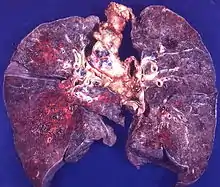

Micoses sistêmicas

.jpg.webp)

Incluem-se neste grupo infecções fúngicas que afetam o sistema respiratório, nervoso, digestivo, circulatório ou osteoarticular. Podem começar como infecção da cutânea ou subcutâneas (por exemplo, Esporotricose e Cromomicose) que se dissemina para outros órgãos ou com esporos (Conídios) inalados (por exemplo, Blastomicose, Criptococose, Coccidiose). Geralmente são oportunistas, afetando portadores de doenças crônicas e imunocomprometidos. [9]